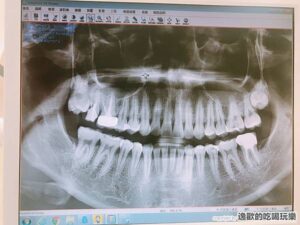

第一次照全口圖發現我真的是牙齒壞光光啊!

因為我沒有在定期看牙的習慣,牙齒只要不痛就應該沒啥太大問題!

上個月有個補牙掉了我也不以為意,過了很久牙齒有感覺才想說要去補一下,原來牙齒有感覺就已經病入膏肓啦!!!

看!我的牙齒原來在補牙的裡面蛀了一個大洞,幸好沒有傷到牙齦可以把它留住,有兩種方式可以治療它,一種是用牙套把我舊有的牙齒蓋住,但是時間久是一定會掉之外不保證裡面的牙齒會不會又開始蛀掉, 所以這次我選擇我人生中第一次的3D齒雕!